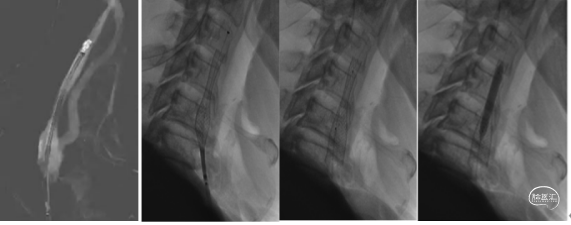

1、经桡动脉通路建设:局麻下置入右桡动脉7F薄壁桡动脉鞘。路图下在0.035in导丝及140cmsim造影导管配合下将7F远端通路导引导管在造影导管引导下到达右侧颈总动脉远端建立通路。下图1

2.置入保护装置:微导丝引入5mm保护伞,路图下将保护伞释放于该侧颈动脉岩骨段近端。下图2、3

3.球囊预扩张:

沿保护伞的微导丝将4mm×30mm球囊置于狭窄段,路图下以工作压缓慢扩张,造影显示狭窄较前改善,退出球囊。

4、支架植入:

沿保护伞导丝置入9mm×40mm Wallstent

支架,下图1、2。支架跨越狭窄段开放良好,残余狭窄,下图3。沿保护伞的微导丝将4mm×30mm球囊置于狭窄段行后扩张一次,回收保护伞,下图4。